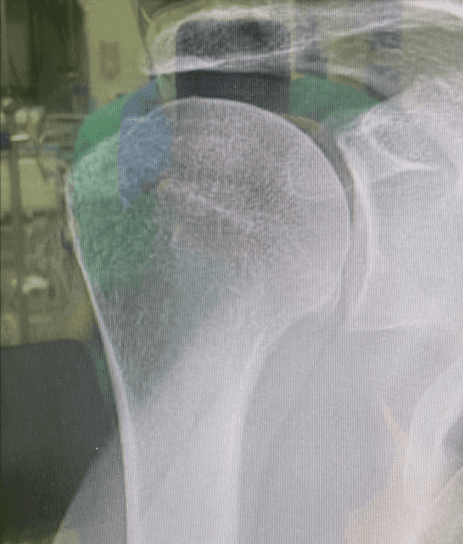

For fracture and revision treatment

The system offers a set of modular Proximal Bodies in several sizes and heights to be paired with a broad range of Modular Stems, available in different diameters and lengths as well as different surface and coating options for cemented and cementless fixation.

The Proximal Bodies’ spiked surface, together with m-l and a-p holes for suture fixation, allow for stable and physiologic tuberosities reattachment. The modular concept of the fracture components supports the surgeon in achieving adequate joint restoration even in cases with poor anatomical landmarks.1